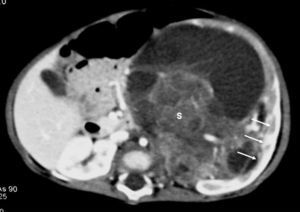

De los 11 nefromas mesoblásticos (con edad y presentación mostrados en la tabla 1) en 7 pacientes el tumor fue sólido y en 4 quístico, con presencia de un polo sólido. En 5 pacientes se encontraron áreas compatibles con necrosis, en dos sangrado intracavitario y en uno función excretora dentro de la masa. Siete pacientes tenían una colección subcapsular y 5 un anillo ecogénico periférico en la ecografía (figs. 1 y 2).

Fig. 1. Nefroma mesoblástico. Niño de 5 meses con masa abdominal palpable. (A) Ecografía abdominal, corte renal izquierdo. Masa en riñón izquierdo predominantemente sólida, con áreas de necrosis (*) y anillo ecogénico en la periferia (flechas). (B) Tomografía computarizada abdominal con contraste intravenoso. Corte al nivel del tercio medio del riñón. Masa en riñón izquierdo que cruza la línea media. Áreas de sangrado (S). Parénquima residual conservado en la periferia posterolateral de la masa (flechas).